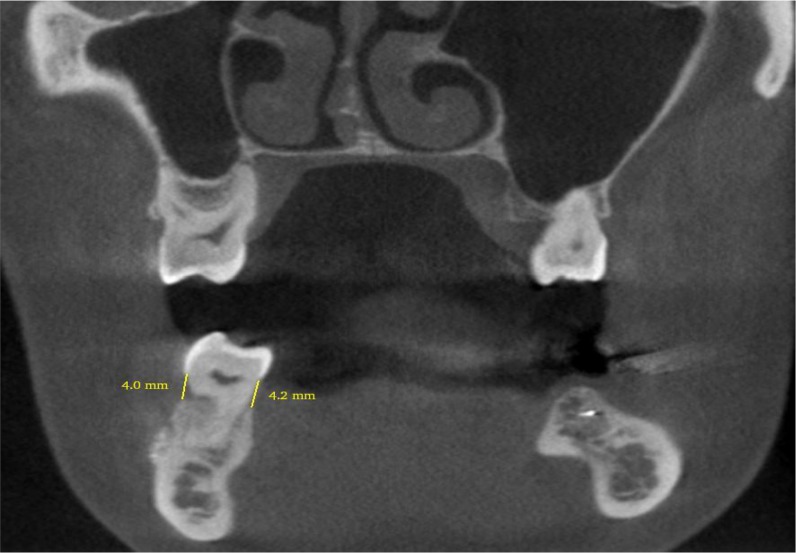

Materials and methods: A study of diagnostic test accuracy was designed and 38 teeth from candidates for dental implant treatment were selected. On CBCT scans, the amount of bone resorption in the buccal, lingual/palatal, mesial and distal surfaces was determined by measuring the distance from the cementoenamel junction to the alveolar crest (normal group: 0-1.5mm, mild bone loss: 1.6-3mm, moderate bone loss: 3.1-4.5mm and severe bone loss: >4.5mm). During the surgical phase, bone loss was measured at the same sites using a periodontal probe. The values were then compared by McNemar's test.

Results: In the buccal, lingual/palatal, mesial and distal surfaces, no significant difference was observed between the values obtained using CBCT and the surgical method. The correlation between CBCT and surgical method was mainly based on the estimation of the degree of bone resorption. CBCT was capable of showing various levels of resorption in all surfaces with high sensitivity, specificity, positive predictive value and negative predictive value compared to the surgical method.